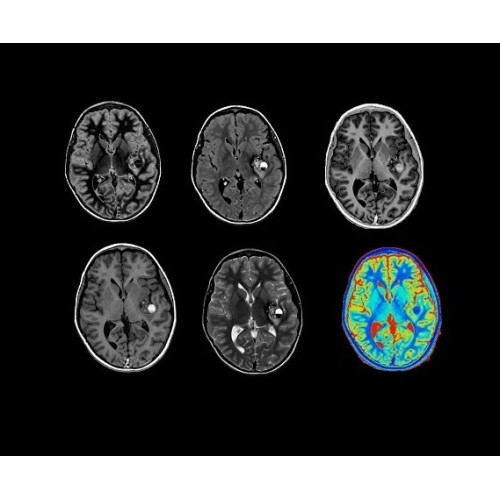

Компания GE Healthcare представляет революционную, полностью интегрированную систему SIGNA PET/MR1, в которой сочетаются времяпролетная технология (TOF) и возможности напряженности магнитного поля 3.0 Тл. Мы поможем вам поднять исследования на более высокий уровень. SIGNA PET/MR позволяет достичь впечатляющей точности и скорости исследований, а благодаря новейшей технологии реконструкции Q.Clear2 качество изображений улучшается в два раза. Кроме того, в систему включен полный набор клинических приложений и гибких катушек для проведения любых видов исследования, открывая для вас возможности визуализации, о которых вы даже не догадывались.

Кроме того, в результате использования технологии TOF и инновационной технологии реконструкции Q.Clear вы сможете добиться прекрасного соотношения сигнал/шум. А благодаря технологии нулевого времени эхо (ZTE) визуализировать костную структуру без ионизирующего излучения. Все эти разработки для улучшения качества сканирования и точности анализа помогут вам использовать весь потенциал ПЭТ/МРТ.

• TurboTOF — инновационная технология позволяет корректировать коэффициент затухания сигнала и минимизировать потери анатомических данных, создавая МР-систему для количественной визуализации.

• Q.Clear — в основу технологии легли накопленные знания о том, как минимизировать помехи при реконструкции и получить четкое изображение. При значительном улучшении качества изображения сохраняется точность расчетов. Сочетание технологии TOF и реконструкции Q.Clear — ваш надежный помощник для получения точных и достоверных данных.

• Специальный пакет приложений для измерения и сравнения объемных изображений ЦНС с нормами поможет вам в диагностике нейродегенеративных заболеваний, а дополнительные инструменты визуализации — в постановке точного диагноза с помощью бета-амилоидов и радиоизотопных маркеров ФДГ.